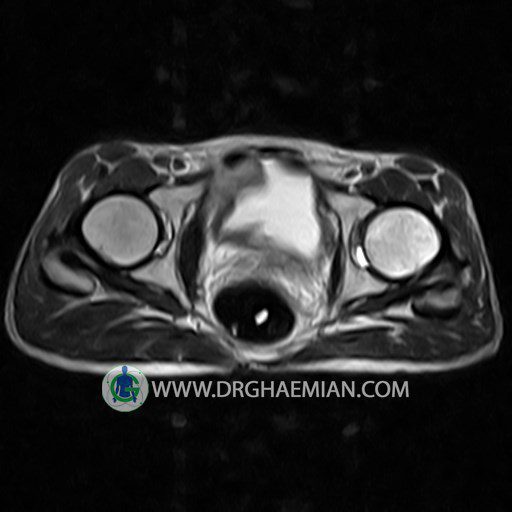

HIP JOINT MRI

( without contrast )

Technique : coronal STIR , coronal T2 , Axial T1 , axial T2 .

REPORT:

The femoral heads and acetabula are normal shape , signal intensity and the femoral heads are well covered by the acetabular margins .

The joint spaces are of normal width without fluid collection .

The articular surfaces are smooth and congruent and show normal cortical thickness .

Each femoral shaft has normal margins and contains a normal bone marrow signal .

The imaged muscles and the lesser pelvis show no abnormalities .

– Heterogeneous signal change (high T2/STIR , low T1) in proximal metaepiphysis of left femur without articular surface irregularity suggestive for bone bruise (stress fracture?), osteomyelitis & arthritis and marrow infiltration (less probable)

– Left hip joint effusion suggestive for synovitis

are seen.

COMMENT: Clinical correlation and MRI with contrast are recommended.